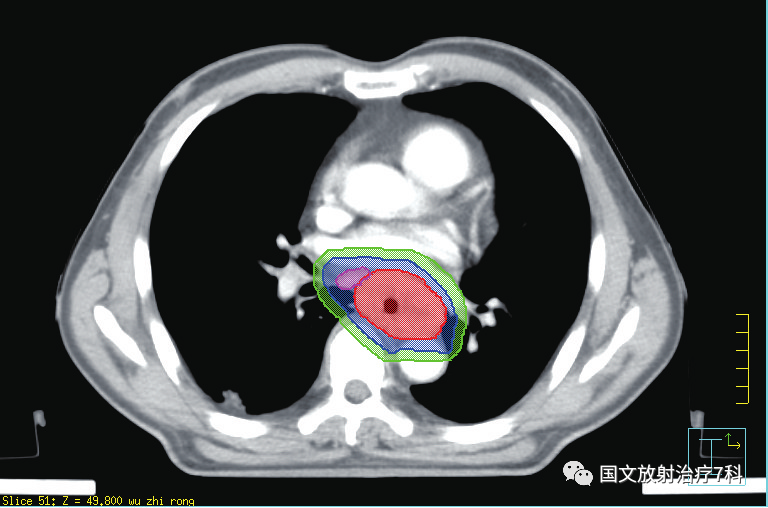

第三步,勾畫靶區(qū)之后,醫(yī)生需要提交治療計(jì)劃,與醫(yī)學(xué)物理師共同完成對(duì)靶區(qū)劑量的設(shè)定,以及危及器官受量的限定。物理師需要借助電腦軟件精確腫瘤患者的放療物理范圍,獲得最優(yōu)的物理劑量分布,做出一個(gè)讓放療醫(yī)生滿意的放射治療方案,為腫瘤患者“對(duì)癥下藥”。 簡(jiǎn)單來講,就是讓射線最大量的照射在靶區(qū)上,最大程度地控制周邊需要保護(hù)器官的射線劑量。靶區(qū)勾畫和治療計(jì)劃確認(rèn)依病情的復(fù)雜程度一般需要3-7天,需要患者的耐心等待。醫(yī)學(xué)物理師是臨床醫(yī)師和大型精密治療器械的銜接單位,有強(qiáng)大的醫(yī)學(xué)物理師團(tuán)隊(duì)是對(duì)治療的充分保障。